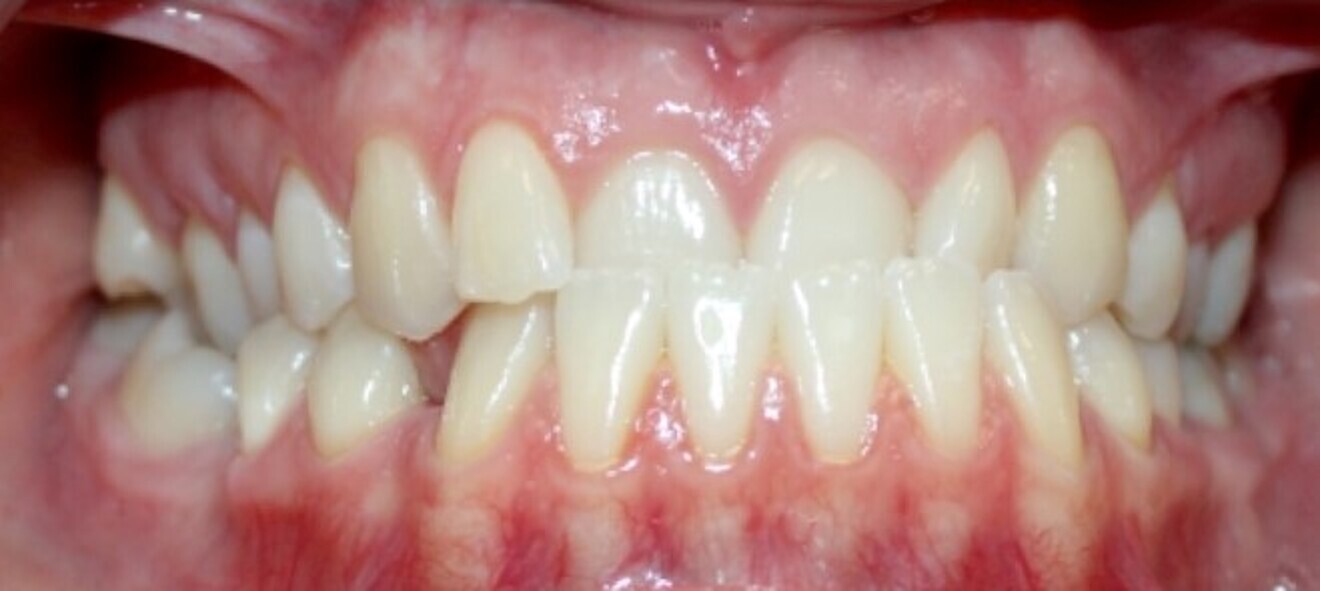

Fig. 20a: Class III malocclusion requiring fixed appliance treatment. (a) Frontal view. (b) Occlusal view.

Fig. 20b: Class III malocclusion requiring fixed appliance treatment. (a) Frontal view. (b) Occlusal view.